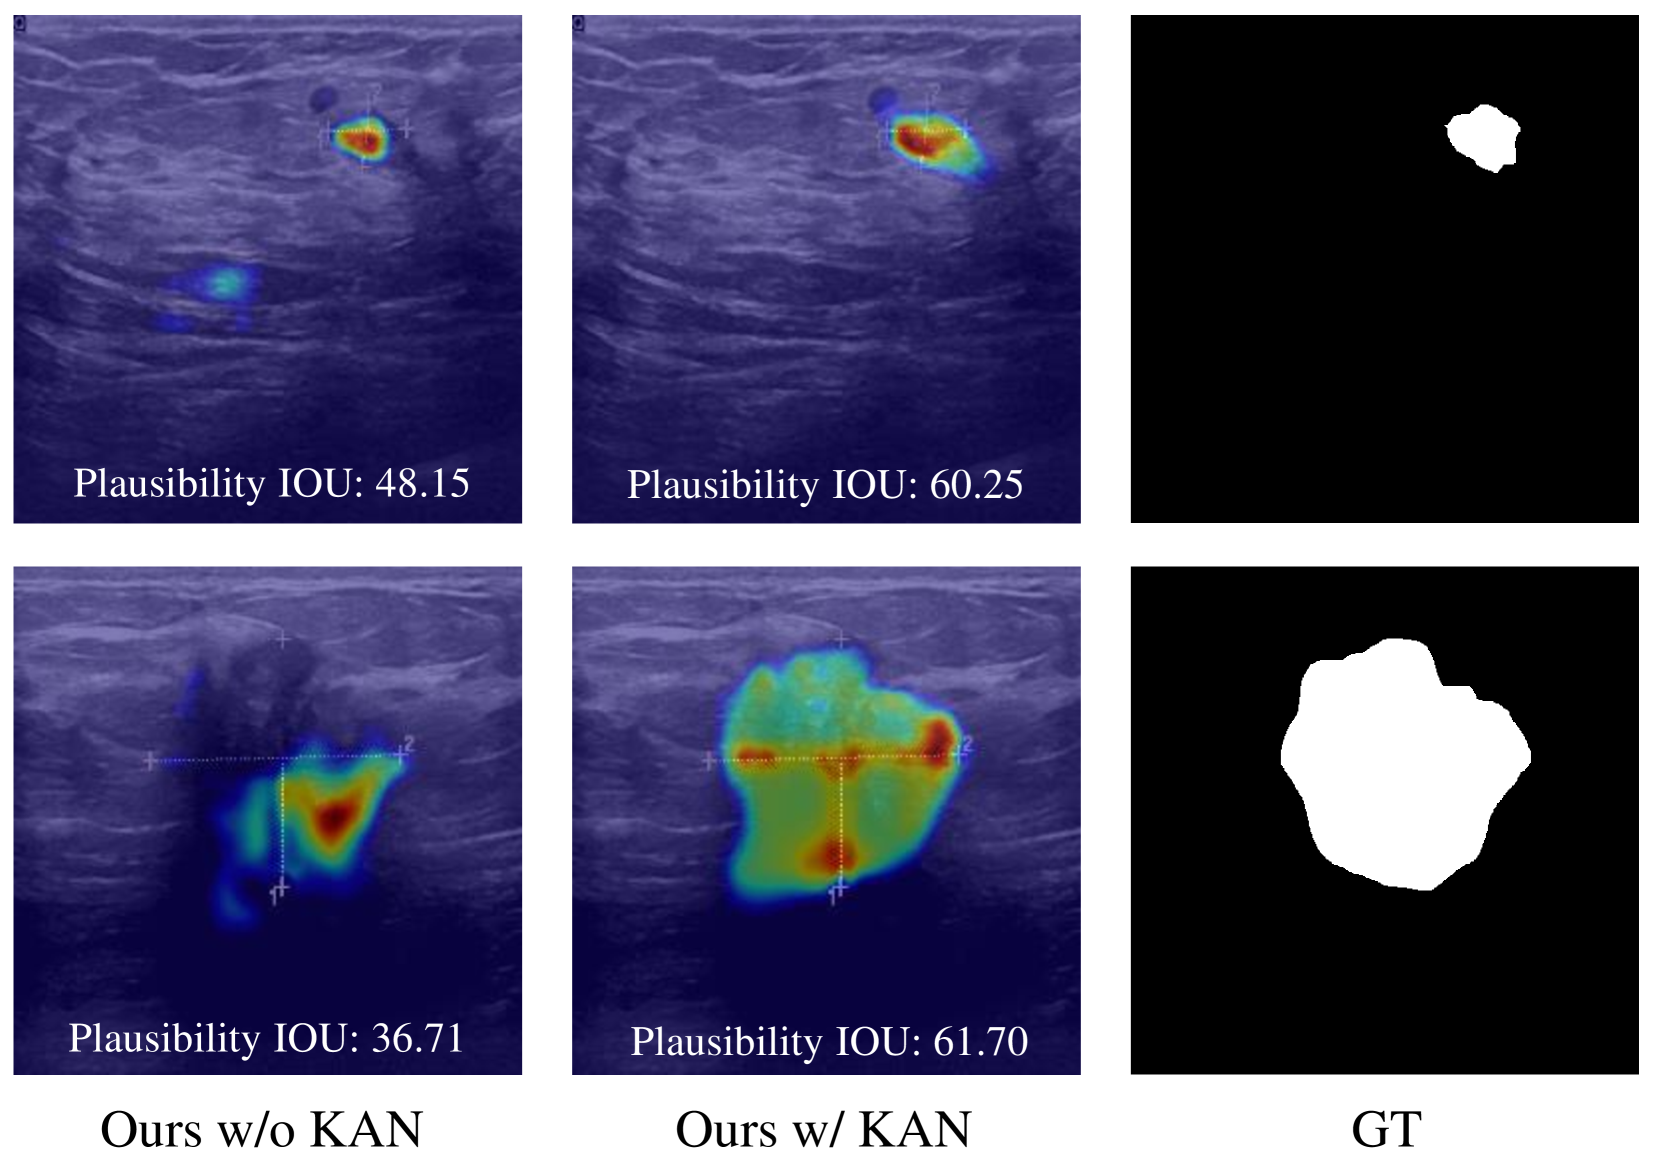

We further explore the interpretability of KAN layers by analyzing activated patterns, as depicted in Fig. 4. When utilizing MLP layers (1th column), the model struggles to identify appropriate activation regions essential with an unsatisfactory Plausibility IoU, which is a metric provided in (Cambrin et al. 2024) that calculates IoU between thresholded activation maps and GT masks (higher is better). In contrast, with integrating KAN layer (2nd column), there is a marked improvement in the ability to precisely locate the region of interest and activate the boundaries that align closely with the ground truth (3rd column). This underscores the pivotal role of KAN layers in enhancing the explainable decision-making of deep models, especially for mask prediction, which is also aligned with the observation in KAN (Liu et al. 2024e).